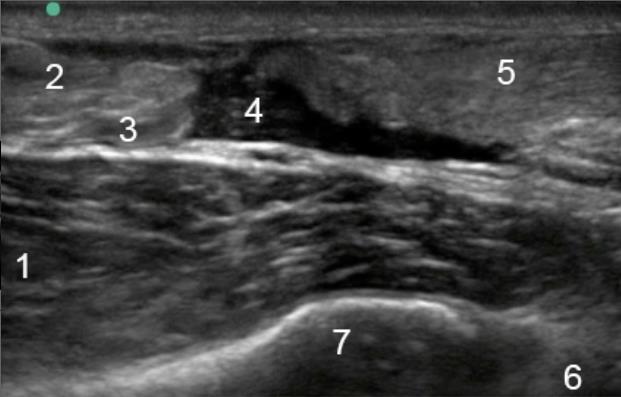

Bild: Fuß und Sprunggelenk, Ruptur d. Achillessehne, longitudinal

1. Flexor hallucis longus

2. Achillessehne

3. Soleus

4. Lücke in der Sehne

5. Achillessehne

6. Talus

7. Tibia